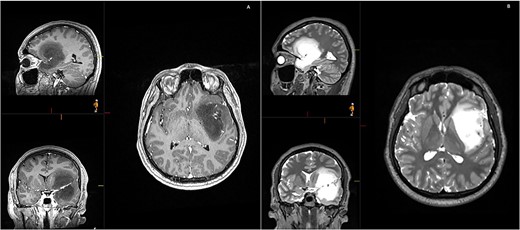

A 28-year-old right-handed man, with unremarkable past medical history, was admitted at the Emergency Department with generalized tonic-clonic seizure with complete post-ictal recovery. The imaging revealed a left frontotemporal insular lesion without contrast enhancement (Fig. 1). A first stage asleep-awake-asleep craniotomy was performed with no complications. The patient remained clinically well throughout admission without neurological deficit. Histology revealed Isocitrate dehydrogenase-mutant grade 2 astrocytoma. Post-operative MRI confirmed residual tumour (approximately 30%), leading to planification of a second-stage surgery.

Initial MRI demonstrating a non-contrast enhancing left frontotemporal insular lesion. (A) T1-weighted post contrast; (B) T2-weighted.